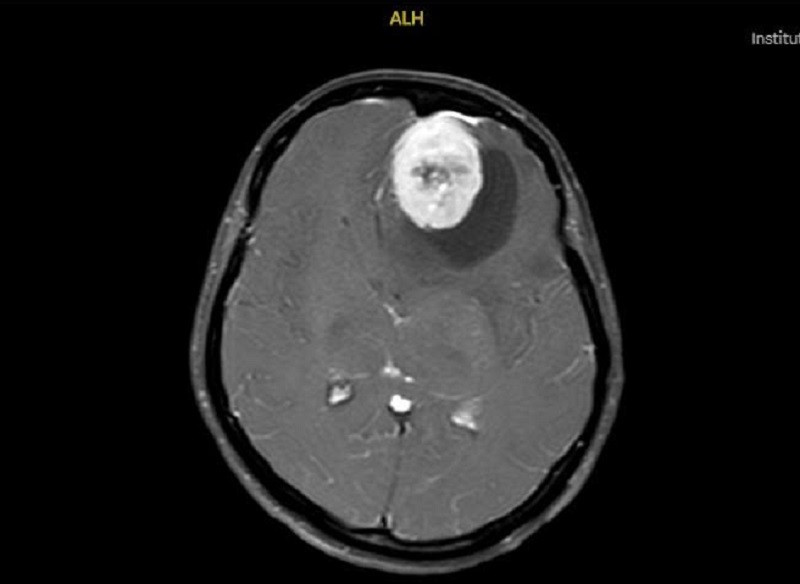

Tại khoa Cấp cứu, sau thăm khám và chỉ định chụp MRI sọ não, các bác sĩ phát hiện một khối u màng não vùng trán có kích thước khoảng 6cm, lớn tương đương một quả trứng gà. Khối u chèn ép mạnh nhu mô não, gây phù não lan rộng và làm lệch đường giữa lên đến 15mm. Đây là mức độ chèn ép rất nặng, có nguy cơ dẫn đến rối loạn ý thức, hôn mê sâu và đe dọa trực tiếp tính mạng nếu không được can thiệp kịp thời.